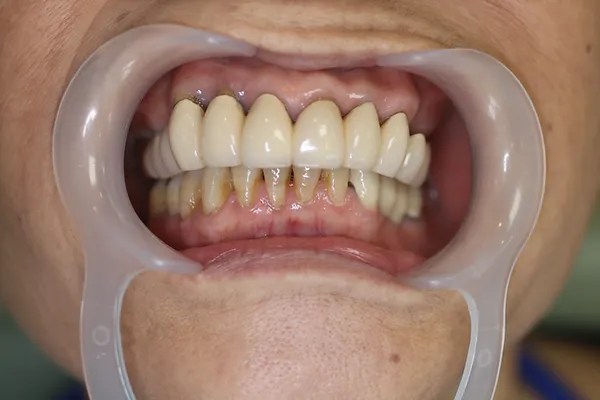

6入れ歯にしないブリッジ治療【ケース2】

H14.12.25のレントゲン

上の歯13本のうち、治療不可能な歯を3本抜き右端から左端までつなげたブリッジを作りました。

H16.1.16に上の歯(ブリッジ)が完成しました。

上の写真は15年以上経過した令和1年11月6日に撮影した写真で経過良好と思われます。